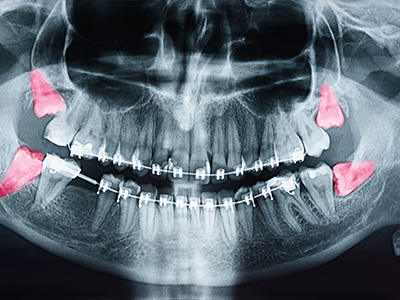

A wisdom tooth is considered impacted when it is submerged under gum tissue or bone and unable to erupt into position. Based on the type and amount of overlying tissue, impactions are classified in a few different ways. Soft tissue impactions occur when a wisdom tooth remains covered by gum tissue. If a wisdom tooth remains completely, or partially obstructed by bone, it's known as a bony impaction.

Impacted wisdom teeth can potentially cause many problems and may need to be removed when they are the source of:

• Pain

• Infection

• Cysts

• Tumors

• Damage to adjacent teeth

• Gum disease

• Extensive tooth decay